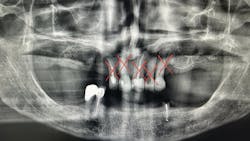

For many older adults, the transition to complete edentulism (figure 1) is both a clinical and emotional hurdle. It often brings feelings of grief, loss of identity, and a gradual detachment from routine dental care. However, this stage should not signal the end of the dental hygienist’s involvement. On the contrary, it requires heightened attention.

While many dental professionals focus on mechanical aspects of dentures—fit, retention, and occlusion—the hygienist’s role extends to soft tissue assessment and early detection of pathology. Some of the most common conditions seen in edentulous patients include (table 1):